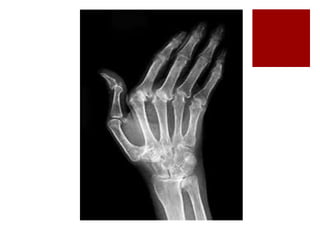

GABINETE -Radiografía

Afección de articulaciones MCF (manos):

Estrechamineto simétrico del espacio articular

Osteoporisis periarticular (rasgo prominente)

Engrosamiento e inflamación de los tejidos blandos

periarticulares (edema y derrame articular)

Erosiones óseas marginales y centrales

Deformidades en cuello de cisne (dedo meñique)

Desviación cubital (aumento del tejido blando en torno al cúbito

distal por edema y engrosamiento del extensor cubital del

carpo)